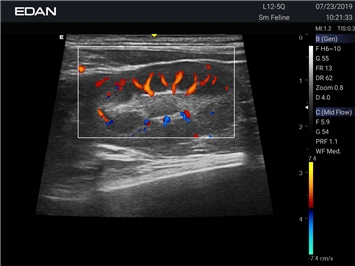

Цветовой допплер:

Да

Энергетический допплер:

Направленный энергетический допплер: